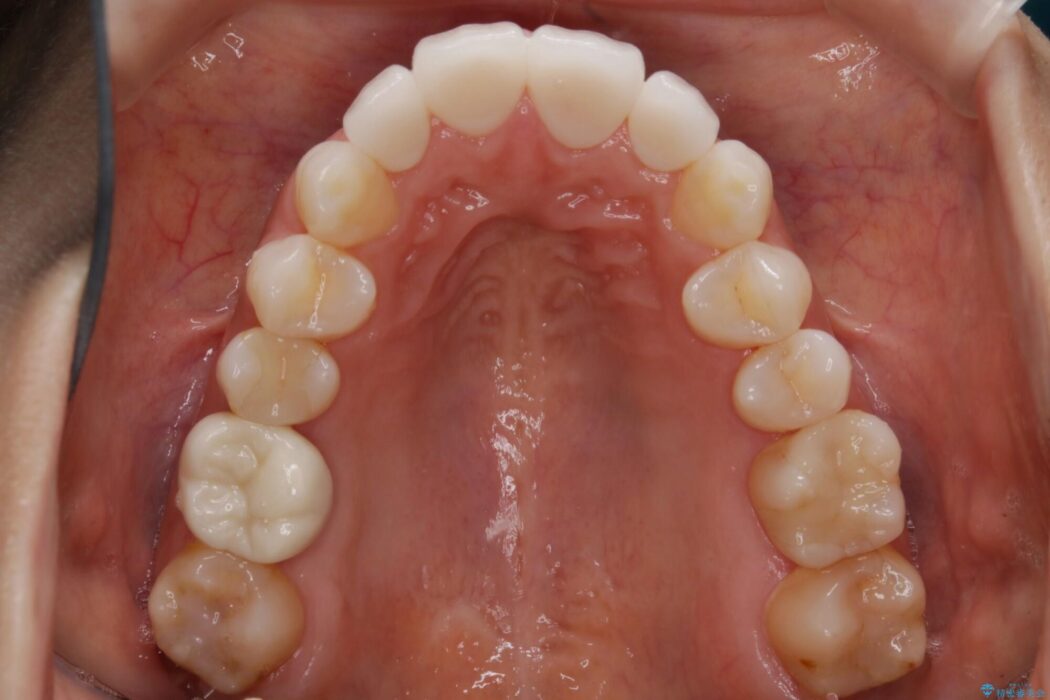

軽度のガタつきと不正咬合が見受けられましたので、インビザラインでの矯正治療を計画しました。

また確認したところ前歯と奥歯にセラミッククラウンで治療した歯があったため、そちらに影響のない範囲内で口腔内全体の噛み合わせが改善されるように歯を動かしていくことになりました。